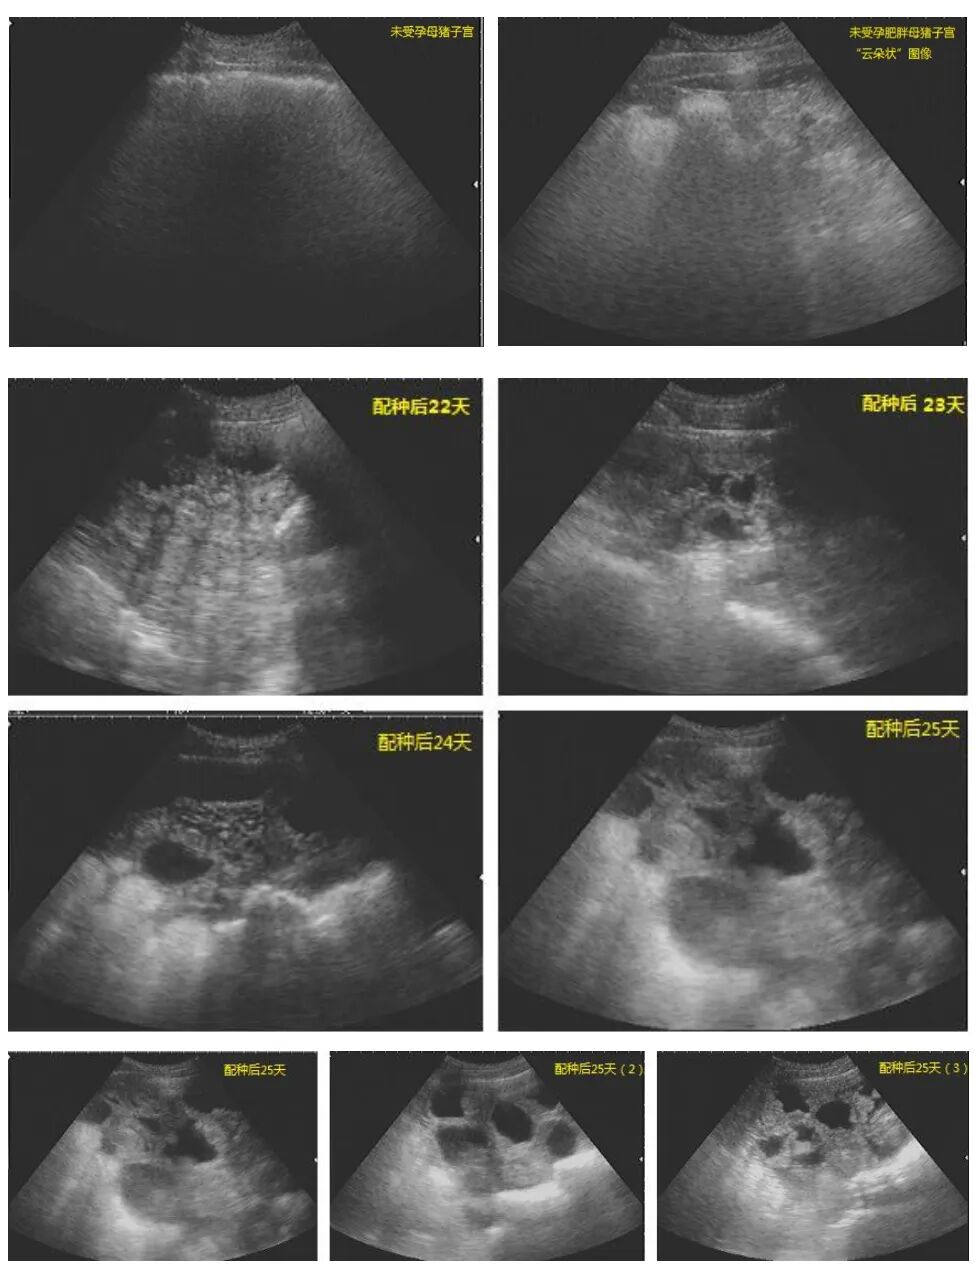

(2)妊娠确认(可选但推荐):配种后第25-30天,用B超复查妊娠,对未孕母猪及时处理,减少饲料浪费。